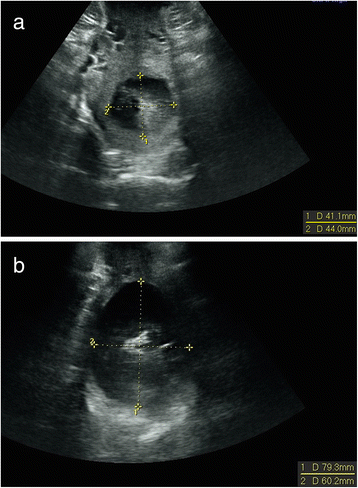

Background: To compare 2D transperineal ultrasound assessment of cervical dilatation with vaginal examination and to investigate intra-observer variability of the ultrasound method.

Methods: A prospective observational study was performed at Skane University Hospital, Lund, Sweden between October 2013 and June 2014. Women with one fetus in cephalic presentation at term had the cervical dilatation assessed with ultrasound and digital vaginal examinations during labor. Inter-method agreement between ultrasound and digital examinations and intra-observer repeatability of ultrasound examinations were tested.

Results: Cervical dilatation was successfully assessed with ultrasound in 61/86 (71 %) women. The mean difference between cervical dilatation and ultrasound measurement was 0.9 cm (95 % CI 0.47-1.34). Interclass correlation coefficient (ICC) was 0.83 (95 % CI 0.72-0.90). Intra-observer repeatability was analysed in 26 women. The intra-observer ICC was 0.99 (95 % CI 0.97-0.99). The repeatability coefficient was ± 0.68 (95 % CI 0.45-0.91).

Conclusion: The mean ultrasound measurement of cervical dilatation was approximately 1 cm less than clinical assessment. The intra-observer repeatability of ultrasound measurements was high.